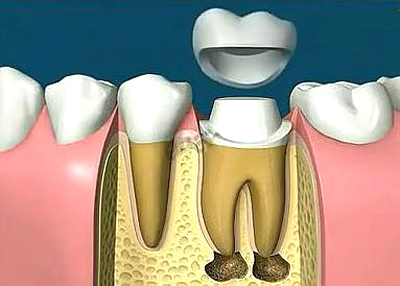

此外,牙科醫院醫生表示,根管治療後是否要做牙冠修複,這也是影響根管治療的一個(ge) 因素,如果需要做,價(jia) 格一般在千多元到數千元不等,因為(wei) 有適合前牙修複的牙冠的,也有適合後牙修複的牙冠,主要看牙齒情況來定。